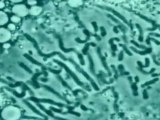

Con seis años, Rocío tuvo varicela y, dos semanas después, le tocó a Mónica. Si a Rocío le empezaba a doler la garganta, a Mónica le diagnosticaban amigdalitis unos días más tarde. Lo mismo ocurría con la gastroenteritis y las incómodas liendres. A ambas les tuvieron que sacar las cuatro muelas del juicio por falta de espacio, pero Mónica tuvo un tipo de conjuntivitis un par de veranos y Rocío no. También se le repetían hongos en la planta de los pies y a Rocío no; y la tuvieron que intervenir de una hernia y a Rocío no le diagnosticaron ninguna. Los gemelos son el mejor experimento natural para medir la influencia de la herencia genética y el ambiente. Ambas son hermanas gemelas idénticas, es decir, comparten el 100% de la información genética, lo que se traduce en el mismo peso, la misma altura y similares facciones. Sin embargo, el organismo de cada una de ellas evoluciona de forma diferente, debido, en gran parte a la epigenética. Sus genes son los mismos, pero su epigenética es distinta. "Se decía que el ADN era el libro de la vida, pero le faltaban las comas, los puntos…, es decir, la epigenética". Manel Esteller, director del programa de Epigenética y Biología del Cáncer del Instituto de Investigación Biomédica de Bellvitge (IDIBELL), define así esta rama de estudio de los genes. Si la genética se detiene en las alteraciones que afectan a la secuencia del ADN, la epigenética se centra en las modificaciones químicas que alteran la expresión de esta secuencia.